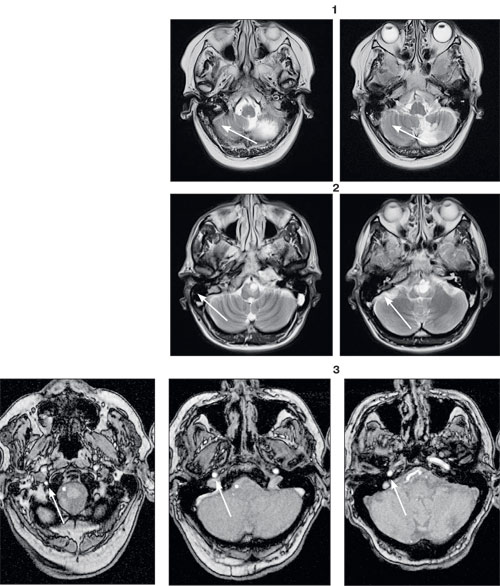

Данные магнитно-резонансной томографии. Инфаркт мозжечка (1), опухоль ствола головного мозга (2), закупорка позвоночной артерии (3) сопровождаются головокружениями.

Центральные вестибулярные нарушения возникают при остром снижении мозгового кровообращения, опухолях, энцефалитах и ряде других заболеваний мозга. Их характер непредсказуем — они могут разбудить ночью, внезапно бросить в сторону на улице или же возникают только при перемене положения головы и тела. Всё это существенно ухудшает качество жизни, снижает активность и работоспособность.